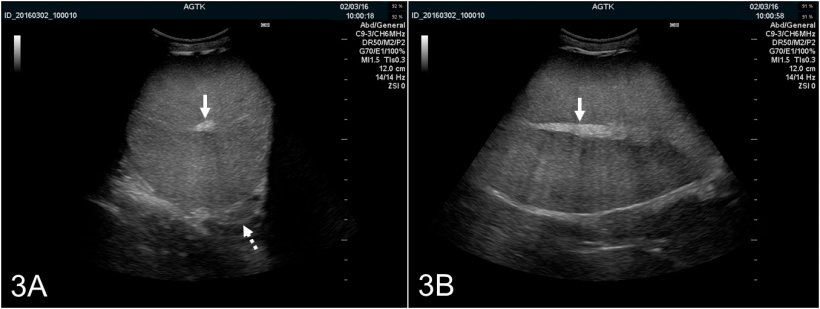

Les testicules peuvent être scannés longitudinalement ou transversalement (Figure 2A et B). Pour déterminer la circonférence testiculaire, des images transversales doivent être utilisées. Le tissu testiculaire sain a une échogénicité moyenne avec une échotexture homogène avec le rete testis hyperéchogène dans le centre du testicule (Figure 3A et B).

Figure 3: Images échographiques du testicule d'un verrat exploré transversalement (A) et longitudinalement (B). Le rete testis est représenté comme une tâche hyperéchogénique dans le centre du testicule (flèche pleine). Le parenchyme testiculaire présente une échogénicité moyenne et une échotexture homogène. L'image transversale donne aussi une visualisation optimale du corps de l'épididyme (flèche pointillée), qui est normalement d'apparence échographique semblable à celle du testicule.